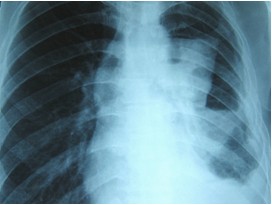

First thing you do is to get the chest x-ray done. The Consult a physician and show him the chest x-ray. If chest x-ray confirms the presence of water, get immediately the ultrasound examination of chest done. If the amount of water collected is between 400 to 500ml millilitres, this water in the chest needs evacuation through syringe-needle under ultrasound or CT- guide. Never allow evacuation of water without the guidance of ultrasound machine, otherwise problem of massive bleeding may occur sometimes.

If the amount of collected water is more than 500 millilitres, consult immediately a thoracic surgeon and have the water in the chest removed with the help of a chest tube. This procedure will prevent the lung from unnecessary trauma and destruction. A chest tube will remove water completely from the chest. Always remember emptying of chest through a chest tube is the simplest and timely method to prevent the destruction of lung.